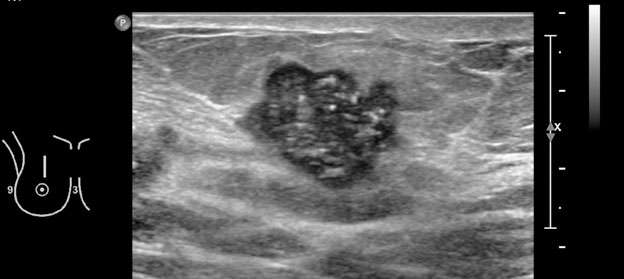

4. Indistinct: There is no clear demarcation of the entire margin, or of any portion of the margin, from the surrounding tissue (Figure 5, Figure 6).

Mammography: Masses Figure 5

Figure 5: Irregular hypoechoic mass with indistinct margin measuring 1.2 x 1.4 x 1.1 cm in the left breast at 1 o'clock, 3 cm from the nipple was visualized with ultrasound, biopsy was recommended. BI-RADS Category: 4C suspicious finding. Pathology confirmed invasive ductal carcinoma with focal lobular features, grade 2.